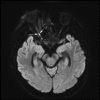

Invasive fungal sinusitis causes painful orbital apex syndrome with ophthalmoplegia and visual loss; the mechanism is unclear. We report an immunocompromised patient with invasive fungal sinusitis in whom the visual loss was due to posterior ischaemic optic neuropathy, shown on diffusion-weighted MRI, presumably from fungal invasion of small meningeal-based arteries at the orbital apex. After intensive antifungal drugs, orbital exenteration and immune reconstitution, the patient survived, but we were uncertain if the exenteration helped. We suggest that evidence of acute posterior ischaemic optic neuropathy should be a contra-indication to the need for orbital exenteration in invasive fungal sinusitis.